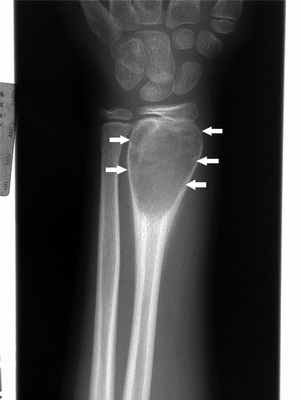

• Как правило, характеризуется вспученностью, но может быть пузырчатой с истонченным кортексом

• Патологический очаг может быть истинно литическим (25—65%); может содержать различное количество минерализованного матрикса

• Неагрессивная, с четкими краями (92%):

о В ряде случаев возможен более агрессивный рост